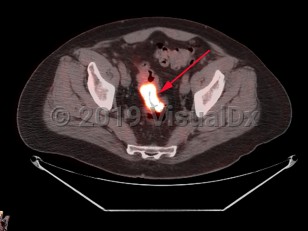

Rectal carcinoma

Patients with cancers of the rectum or rectosigmoid region often present with hematochezia, tenesmus, and narrowing of the stool. Anemia is uncommon at presentation.